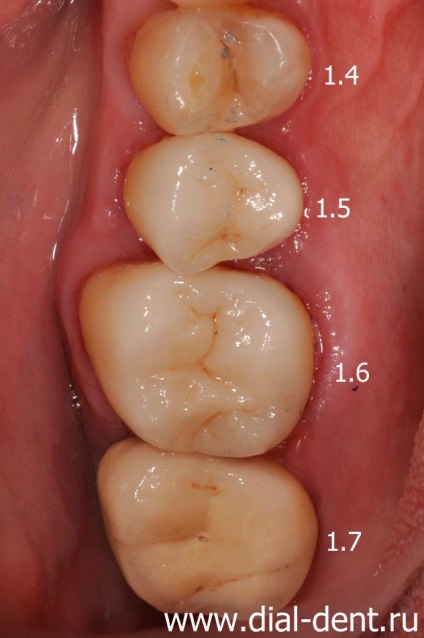

Rezultat stomatologie integrat

Rezultatele tratamentului la Centrul stomatologic de familie „Dial-Dent“ a fost restaurarea completă a funcției și aspectul dinților de mestecat:

Dinții 1.4, 4.5 - sigiliu de lumină.

Dinții 1.5, 1.6, 4.6, 4.7 - coroane ceramice.

1.7 dinte - cape coroană și cermet.

coroane ceramice sunt realizate din ceramica presata e.max. Ceramica e.max - ceramică durabilă modernă este aplicată tuturor dinților grupurilor protetice, deoarece în afară de caracteristicile estetice înalte prezintă o rezistență excelentă și rezistență la așchiere. Coroanele dentare în stomatologie modernă este folosit tot mai mult, deoarece acestea nu provoacă reacții alergice și fenomene galvanismului, nu există nici un răspuns de la gingii.

După montarea de coroane permanente, acestea au fost înregistrate cu ajutorul cimentului rășină modernă folosind sistemul batardouri. să excludă complet pătrunderea umezelii sub coroana. uscăciune absolută în timpul fixarea coroanelor dentare imbunatateste calitatea protezare, extinde durata de viață a coroanelor dentare.